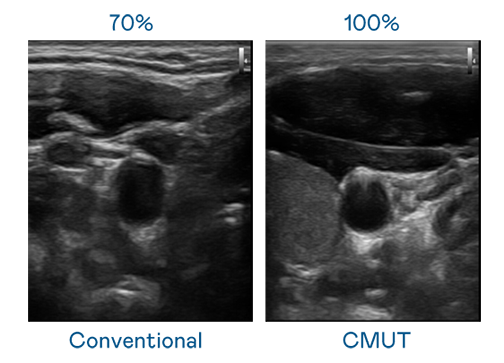

CMUT 技术是一种用电容式微机电元件来产生超音波讯号的技术。与传统 PZT 压电式技术相比,CMUT 频宽增加 30%,更宽频的超音波讯号让影像解析度大幅提升,是实现高影像品质医疗超音波扫描、促进精准医疗发展的关键技术。

大频宽带来超清晰影像

超音波影像的解析度高低,首先取决于探头能发出的讯号频宽。IM电竞 CMUT 可提供高清晰的超音波讯号,提供高频宽、高灵敏度、影像纹理细节更高的超音波影像,协助医护人员缩短影像判读时间及利用精准的医疗影像进行诊断。